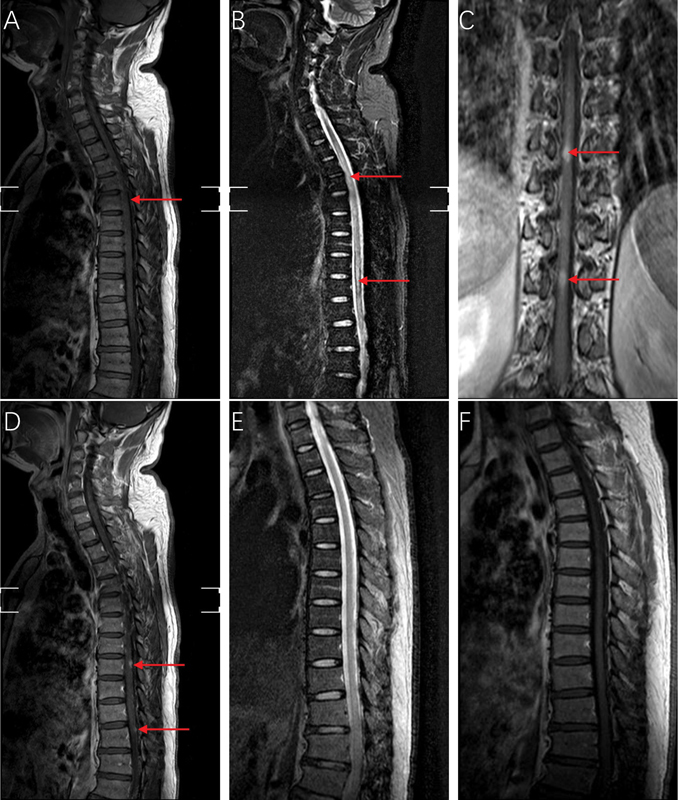

In this article, we presented an exceedingly rare clinical case of neurosyphilis, radiological revealed a distinctive "candle guttering appearance." Posttreatment for syphilis, both clinical symptoms and radiological markers showed complete resolution.